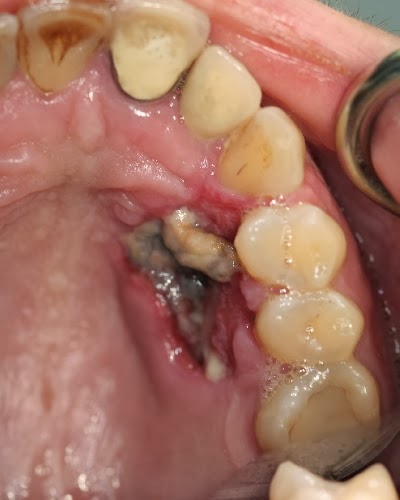

Osteoradionecrosis of the jaw

This is one potentially severe complication that can necessitate surgical intervention and reconstruction. It is a severe iatrogenic disease of devitalized bone caused by RT of head and neck cancer and can occur during or after treatment. It is a state of injured bone tissue with inadequate healing or remodeling response of at least three to six months. Bone loss or death is the result of damaged blood vessels within the bone. It can cause bone fracture and infection.

Depending on the location and extent of the lesion, symptoms may include pain, bad breath, taste distortion (dysgeusia), “bad sensation”, numbness (anesthesia), trismus, difficulty with mastication and speech, fistula formation, pathological fractures, and local, spreading, or systemic infection. Patients who have received high-dose radiation to the head and neck are at lifelong risk for osteoradionecrosis, with an overall risk of approximately 15%.

The jaw bone (mandible) is the most frequently affected bone, especially in those treated for nasopharyngeal cancer. Maxillary involvement is rare because of the collateral blood circulation it receives.

Tooth extraction and dental disease in irradiated areas are major factors in the development of osteoradionecrosis.  In some cases it is necessary to remove teeth before RT if they will be in the area receiving radiation and are too decayed to preserve by filling or root canal. An unhealthy tooth can serve as a source of infection to the jaw bone that can be particularly difficult to treat after radiation.

Repair of nonrestorable and diseased teeth prior to RT may reduce the risk of this complication. Oral disease should be eliminated pretreatment whenever possible. Dentition that exhibits poor prognosis and is within high-dose radiation fields should be extracted before RT begins. Ideally, at least 7 to 14 days should be allowed for healing before initiation of RT; some have suggested allowing up to 21 days.